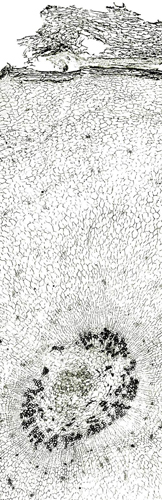

内部形態:鏡検

本品はほぼ偏球形を呈し、径1~2cmで、一端に茎の跡がある。外面は灰黄色~灰褐色で質は堅く、破砕面は黄色で平滑または灰黄緑色で粒状である。 本品はほとんどにおいがなく、味は苦い。 Corydalis属は、39節、約428種が広く世界に分布するといわれ、このうち38節,約288種が中国に分布している。このうち塊茎をつくるものは4節であり、分布が局地に限られるものを除くと、Sect. Duplotuberと Sect. Pes-gallinaceus の2つの節に限られる。Sect. Duplotuber にはチョウセンエンゴサク C. ternata (Nakai) Nakai (C. nakaii Ishidoya) および、ジロボウエンゴサク C. decumbens (Thunb.) Persが含まれる。Sect. Pesgallinaceusには C. yanhusuo Wang ex Su et Wu (C. turtschaninovii Besser forma yanhusuo Y. H. Chou et C. C. Hsu)が含まれるとされている。 |

内部形態の比較(市場品)

浙江省産市場品の横切面では、形成層は明瞭で環状につながっている。道管は形成層の近くに散在しており、中央に髄がある。コルク層を表面視するとコルク細胞は厚膜の長条形である。 韓国産市場品の横切面では、維管束が放射状に配列し、形成層は不明瞭で放射組織によって分断され、環状につながらない。コルク層を表面視すると、コルク細胞は薄膜の多角形である。

部位による内部形態の比較 ①

兵庫県柏原における試験栽培品(浙江省産を種付け)は浙江省市場品と同様の形態を呈していた。 <横切面> ・形成層は明瞭で環状につながる。 ・道管は形成層の近くに散在している。 ・中央に髄がある。

| ○試験栽培品 (種塊茎/親) |

○試験栽培品 (新塊茎/子) |

○試験栽培品 (塊茎間) |